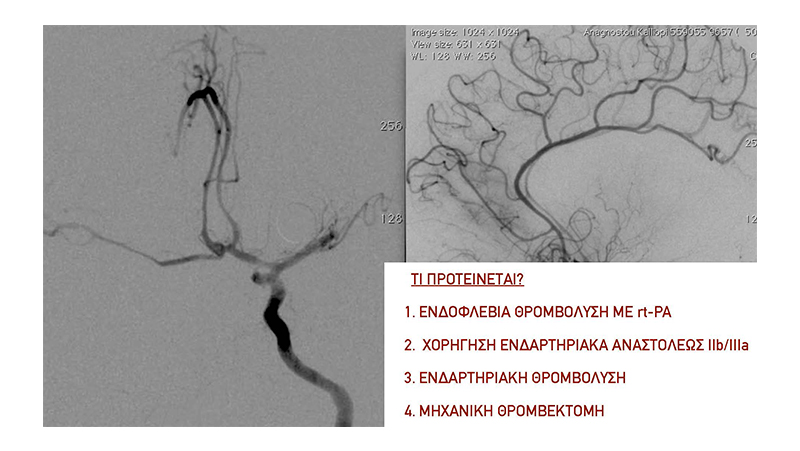

Εικόνα 2: Έγινε εμβολισμός του ανευρύσματος στην οξεία φάση με coils. Στην τελική αγγειογραφία, φαίνεται η πλήρης απόφραξη του ανευρυσματικού σάκκου. Διακρίνουμε όμως και την απόφραξη του Μ1 της αριστεής μέσης εγκεφαλικής αρτηρίας, από θρόμβο που πιθανότατα αποσπάστηκε από την αυχενική έσω καρωτίδα κατά τους χειρισμούς (σημειωτέον ότι η επέμβαση έγινε χωρίς ηπαρίνη επειδή το ανεύρυσμα ήταν ραγέν.

Εικόνα 3: Αγγειογραφία της αριστερής έσω καρωτίδος σε προσθιοπίσθια και πλάγια προβολή: Διακρίνεται η απόφραξη του τέλους του Μ1 τμήματος της μέσης εγκεφαλικής αρτηρίας.